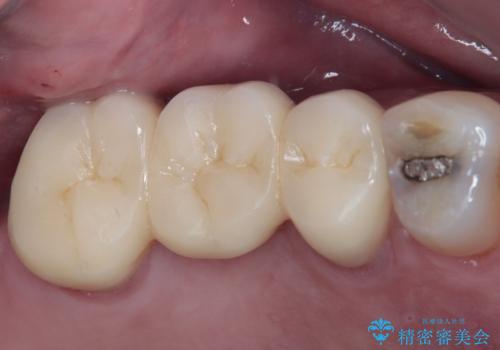

目立つ銀歯をセラミッククラウンに

【セラミッククラウン】詰め物と歯の境目に汚れが溜まる